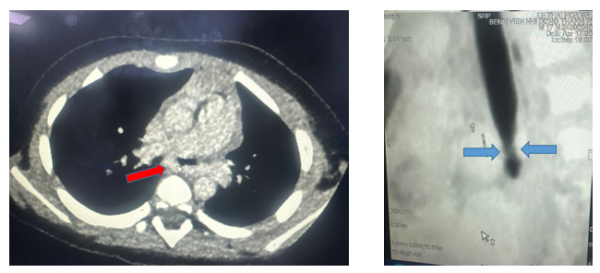

| CT scan ngực mặt cắt ngang thấy động mạch phổi trái quấn hẹp khí quản gốc, mặt cắt dọc đứng thấy hẹp khí quản gốc (carina). Ảnh BVCC |

Tại đây bệnh nhi được tiếp tục điều trị như cơn hen phế quản nặng, tình trạng trẻ có cải thiện nhưng vẫn còn khò khè nên được hội chẩn chụp CT scan ngực có cản quang, ghi nhận khí quản gốc chỗ chia đôi phế quản phải trái (carina) có động mạch phổi trái vòng qua phải ôm lấy rồi đi qua phổi trái, gây chèn ép đường thở.